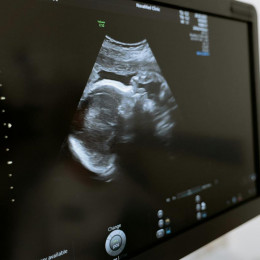

Evropski poslanci bodo danes glasovali o državljanski pobudi My voice, my choice – Moj glas, moja izbira. Komisija škofovskih konferenc Evropske unije (COMECE) ob tem opozarja, da je urejanje ...